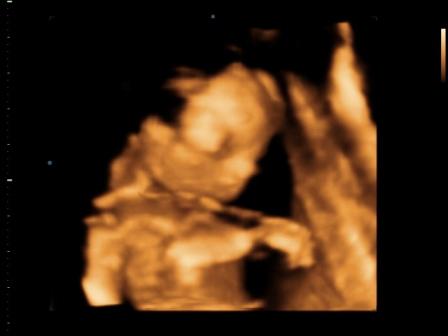

Mamacka neked nagyon profi képeket csináltak, főleg az arcáról! Koutchnak pedig a fütyiről! :)

mi is megjöttünk, minden ok. nagyon szégyenlős volt, szinte semmit nem mutatott az arcából. a placentát, mint egy kismama a szopipárnát ölelte, és jól odabújt. amúgy egészséges, pöckét mutogatta, így nekünk is tuti a fiú. auszrtál volt az uhás nő, jófej volt, alapos.

CD-t én is kaptam, képeket minnyá nézek róla. Ja, a képek nálam se lettek nagyon jók, mert ő is belefúrta magát a lepénybe. Ettől függetlenül szépen látszott, ahogy integet, kalimpál, fogja a fejét stb.

Jó volt, sokáig nézték a babócát, egy nagyon profi géppel, ahol mindenféle áramlást is vizsgáltak (pl.: főerek, köldökzsinórban lévő áramlást-itt még hang is volt, nagyon érdekes volt). Megnézték még egyszer a nemét is, és 100%, hogy kisfiú! Sokat mosolygót a baby, de végére elfáradt, és bújt el a kezei mögé, nagyon cuki volt!